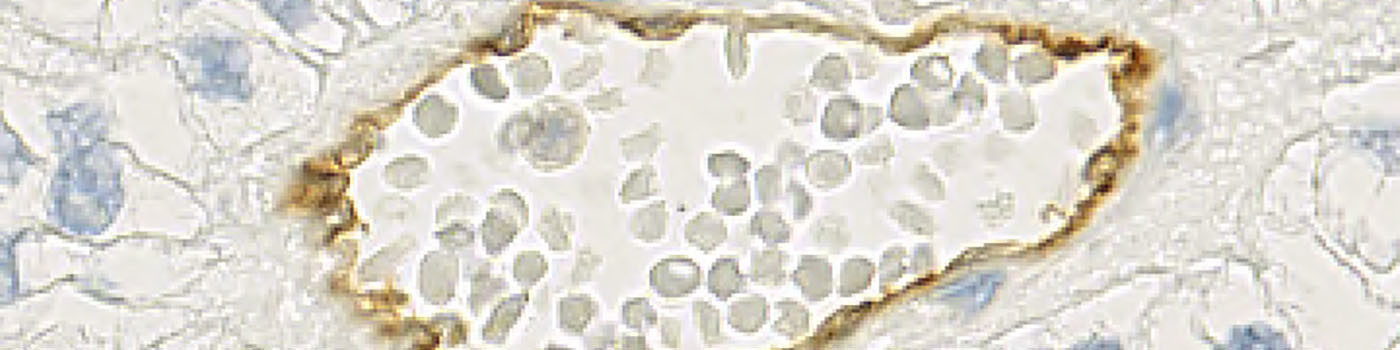

It is of interest to define the differences between these two groups. One of the differences that are examined is the degree of maturity of the microvessels. For this purpose the vessel markers CD31 and CD34 are used. Since CD31 is a marker for mature vessels, CD34 positivity in the absence of CD31 can be used to identify more immature vessels.

The purpose of this APP is to quantify the CD31 positive areas, CD34 positive areas, and overlapping positive areas to investigate if the ratio of mature to immature vessels is one of the differences between the responder and non-responder groups.

From a TMA block, sequential slides were obtained and each slide was stained with either CD31 or CD34 (see FIGURE 1). Using the patented Autodisector technology, the two sequential slides can be overlaid (see FIGURE 2) and each TMA core-pair is automatically aligned at a high magnification, cell-to-cell level, to facilitate the detection of overlapping positive stain between the two slides (see FIGURE 7).

The images that are obtained from the alignment procedure are two-layered TIFF files. In each image, the first layer is the CD31 stained core and the second layer is the CD34 stained core. The layers are referred to as frame 1 and frame 2 in the software.

Based on a DAB color deconvolution, (see FIGURE 5), the positive stain areas are identified as areas where the stain density is higher than a certain threshold. This leads to a segmentation of the image using three labels: